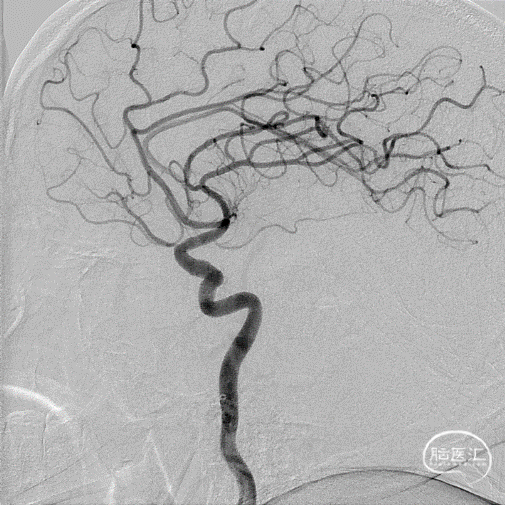

术前DSA影像:造影显示患者右侧大脑中动脉闭塞。

DSA—主动脉弓造影

右侧颈内动脉造影—M1段闭塞